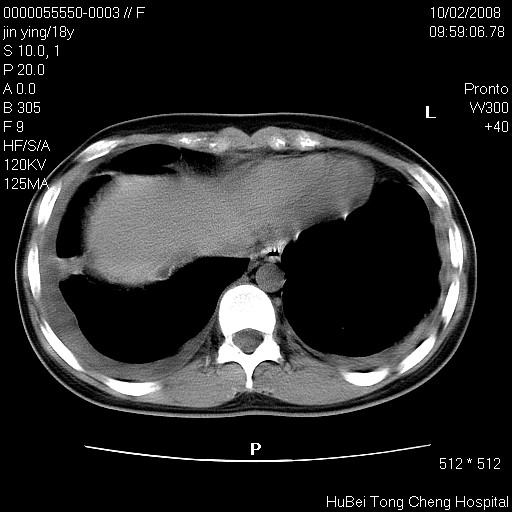

患者 女,18y。发热十余天,伴咳嗽。pe:t39⒈℃,bp 110/80mmhg,p 86次/min。神清,精神欠佳。双肺可闻及少许湿罗音。既往史不详。

临床诊断:肺部感染?

胸部ct轴位平扫(层厚10mm,螺距1.5,重建间隔10mm),图像如下: